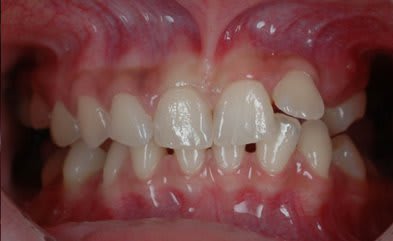

SI joint les photo intra buccal pre traitement et pendant traitement.

Comment expliquer vous le développement ce canting en frontal et de l'open bite en Postérieur ?

Qu'elle est la source du mal ?